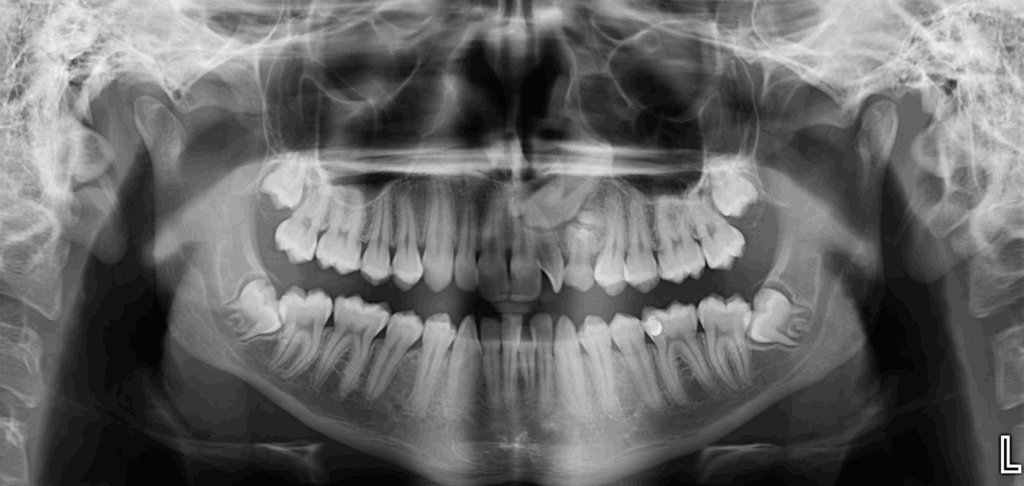

En la radiografía panorámica (Figura 1), se aprecia imagen radiopaca circunscrita con un halo radiolúcido, de limites definidos, proyectado en tercio medio y apical de pieza 53, observándose en el interior múltiples dentículos.

Radiografia Panorámica